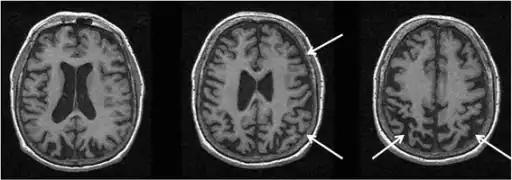

MRI showing right greater than left parietofrontal atrophy

MRI

MRI images are useful in displaying atrophied portions of neuroanatomical positions within the brain. As a result, it is especially effective in identifying regions within different areas of the brain that have been negatively affected due to the complications associated with CBD. To be specific, MRI of CBD typically shows posterior parietal and frontal cortical atrophy with unequal representation in corresponding sides. In addition, atrophy has been noted in the corpus callosum.[19]